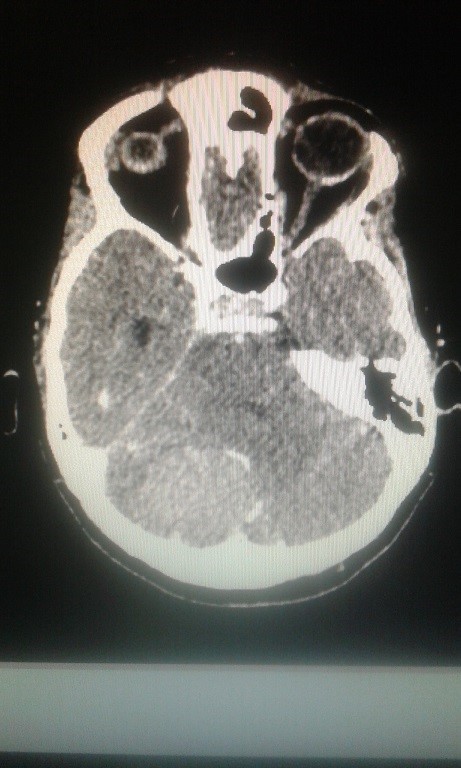

Volver a los detalles del artículo Meningioma incidental del tentorio